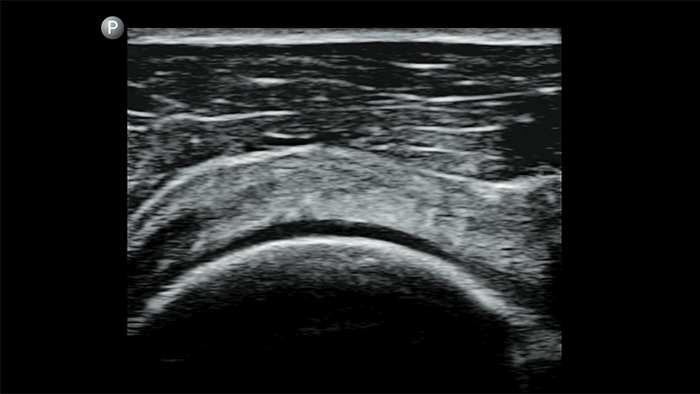

Reduzca las complicaciones en procedimientos guiados por aguja

El ultrasonido portátil Lumify para anestesiología le ayuda a visualizar claramente la definición de los bordes con la colocación de la aguja, los nervios circundantes, los vasos sanguíneos y los planos fasciales.